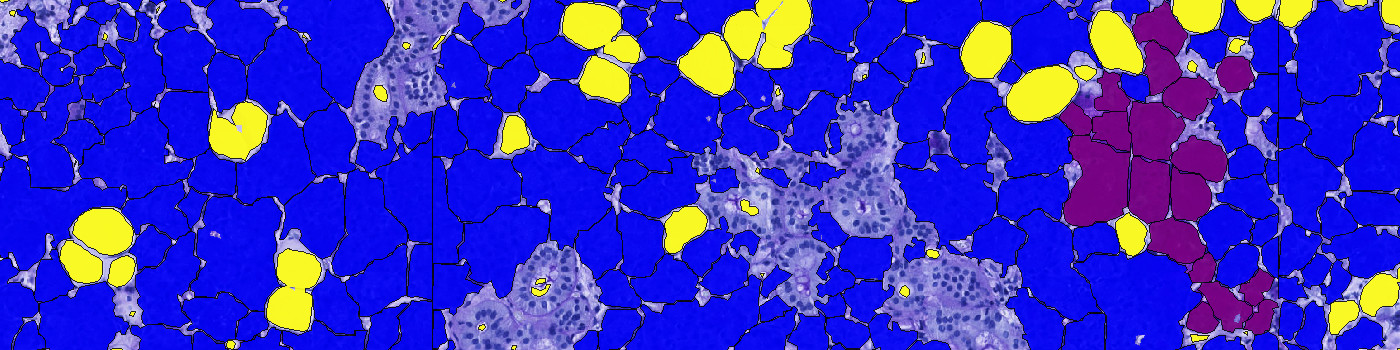

Salivary glands stained with CKAE1/AE2. The blue ROI shows automatic detection of glandular region.

The protocol works on a virtual double stain (VDS) of PAS and CK AE1/AE2 stained serial sections. Initially, the outer boundary of the glandular area is outlined by thresholding the brown feature HDAB-DAB of the CKAE1/AE2 slide. FIGURE 1 and 2 show the aligned sections with outline. In case of artefacts, such as tissue folds etc., the outline should be manually corrected.

Glandular areas within the ROI are classified by thresholding the intensity of the CK AE1/AE2 slide, providing a ratio of glandular tissue to connective/adipose tissue. The classification of glandular tissue is shown in green in FIGURE 3 and 4.

Finally, the ROI in the PAS slide is classified into mucous glands, serous glands, adipose tissue, and connective tissue/export channels. The classification of serous glands, adipose tissue, and connective tissue/export channels is based on the red intensity, while the mucous glands are classified based on an H&E Eosin feature. The classification is seen in FIGURE 5 and 6. The areas of mucous glands, serous glands, adipose tissue, and connective tissue/export channels are calculated for each class.